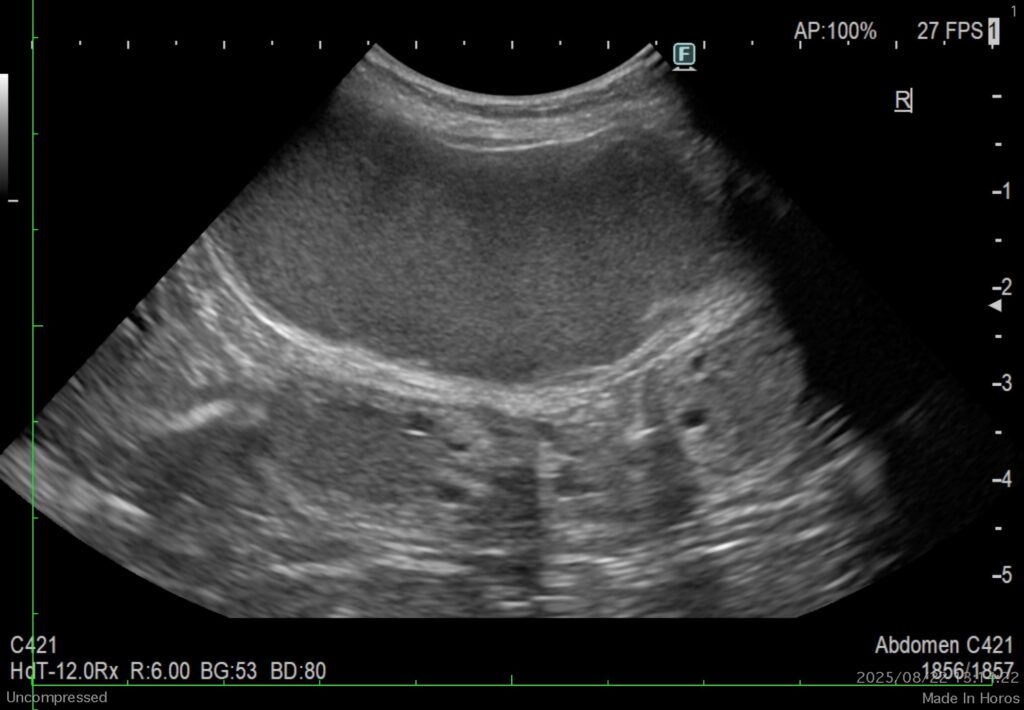

超音波検査で子宮内拡張所見あり(内容物の混濁)、膀胱内に3cm大の結石(他砂粒状の石も多量)。